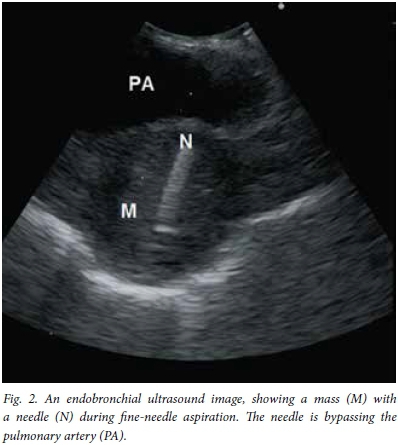

A 67-year-old man with a 40 pack-year smoking history presented with a 2-year history of hoarseness and weight loss. He also had a history of asbestos exposure. On examination under anaesthesia a lesion of the right false vocal fold was found and histology showed a moderately differentiated infiltrating keratinising squamous carcinoma. A subsequent computed tomography (CT) scan provisionally staged his supraglottic carcinoma as T2N0M0 and he underwent radical treatment with external beam radiation therapy, to which he responded well. He had been attending our clinic regularly and remained well, but on a visit 4 years later possible recurrence was considered - with hilar lymphadenopathy noted on his chest radiograph. On the CT scan of his chest there was a heterogenously enhancing soft-tissue mass (42 mm x 30 mm) in the posterior segment of the left upper lobe, adjacent to the proximal descending thoracic aorta, with a tissue plane between the mass and mediastinal structures appreciated. The mass demonstrated encasement of the left main pulmonary artery (Fig. 1). There was also a left diaphragmatic calcified plaque. The question posed was whether this mass could be ascribed to metastatic supraglottic carcinoma or if it was indeed a metachronous primary bronchus carcinoma, as the treatment of these two malignancies differs significantly. Considering traditional bronchoscopy with TBNA as the least invasive procedure to obtain a cytological diagnosis, the proximity of the aorta and pulmonary arteries and the mass being 14 mm from the bronchus would have made sampling by means of this procedure near impossible. With the assistance of EBUS the mass was localised, despite it not abutting the bronchus, and the position of the major vessels duly noted on Doppler ultrasound. Under real-time ultrasound guidance (Fig. 2) the tissue plane between the mass and bronchial lumen could be bridged by the longer EBUS needle to traverse safely between the major vessels, a window of <10 mm, and obtain a fine-needle aspirate of the mass. The result, which proved to be a keratinising squamous carcinoma (Fig. 3), was most likely of supraglottic origin. The patient was discharged the same day, with a follow-up appointment to see an oncologist.